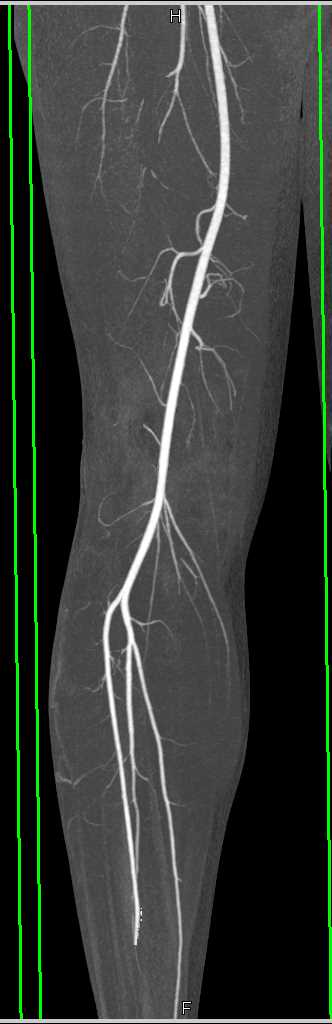

Ulceration with Intramural Hematoma Descending Aorta